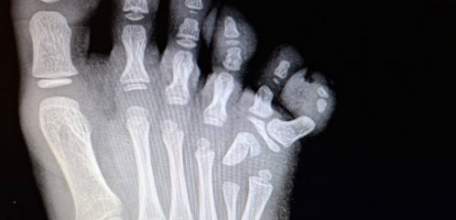

Елецкие врачи провели сложнейшую операцию малышке с аномалией развития стопы. У девочки с рождения был шестой пальчик на ножке!

Врачи елецкой детской больницы буквально по кусочкам собрали стопу 17-летнего парня